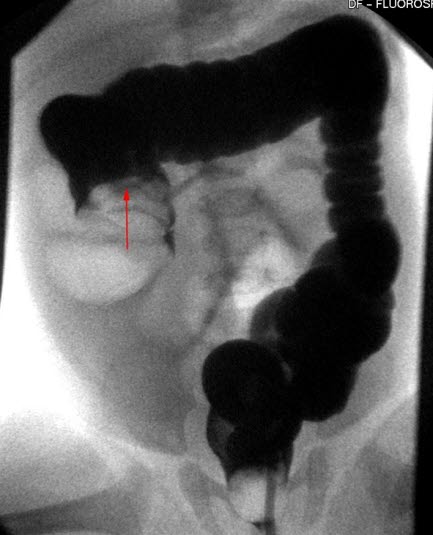

Enkelkontrastundersøkelse av tykktarmen. Terminale ileum og coecum har vrengt seg inn i colon ascendens (pil). Ofte kan man ved hjelp av trykket fra colonkontrasten reponere invaginasjonen